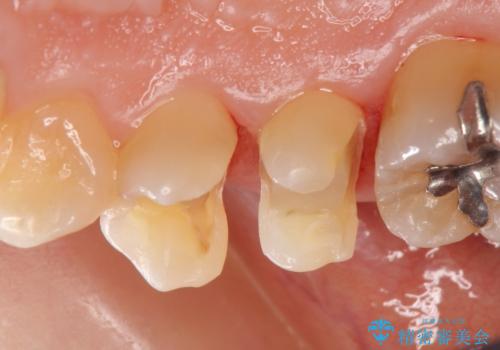

- 右上4番目の歯がしみるといらっしゃった方の症例です。

古い樹脂を除去後、セラミックインレーによる修復を行いました。